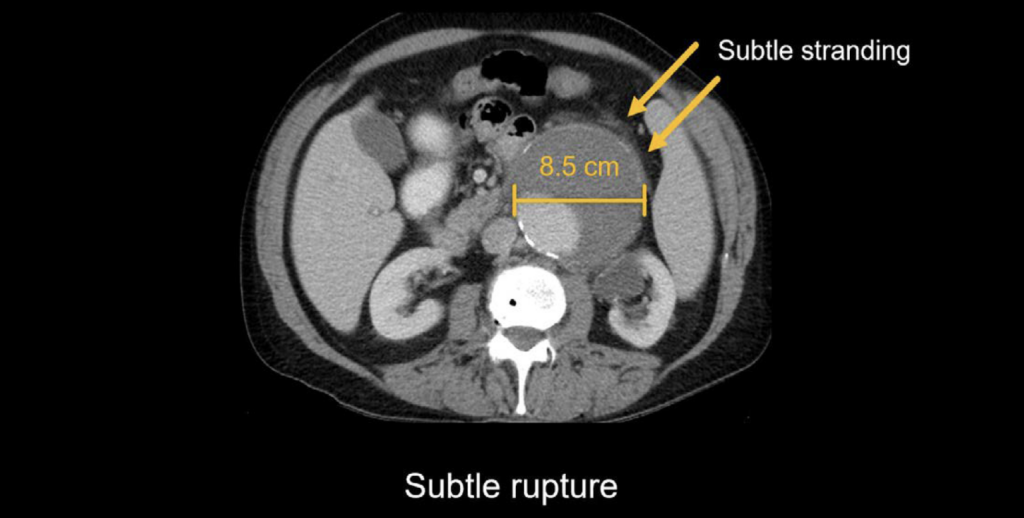

Abdominal CT Aortic Aneurysm LITFL Radiology Library

Abdominal CT Aortic Aneurysm LITFL Radiology Library